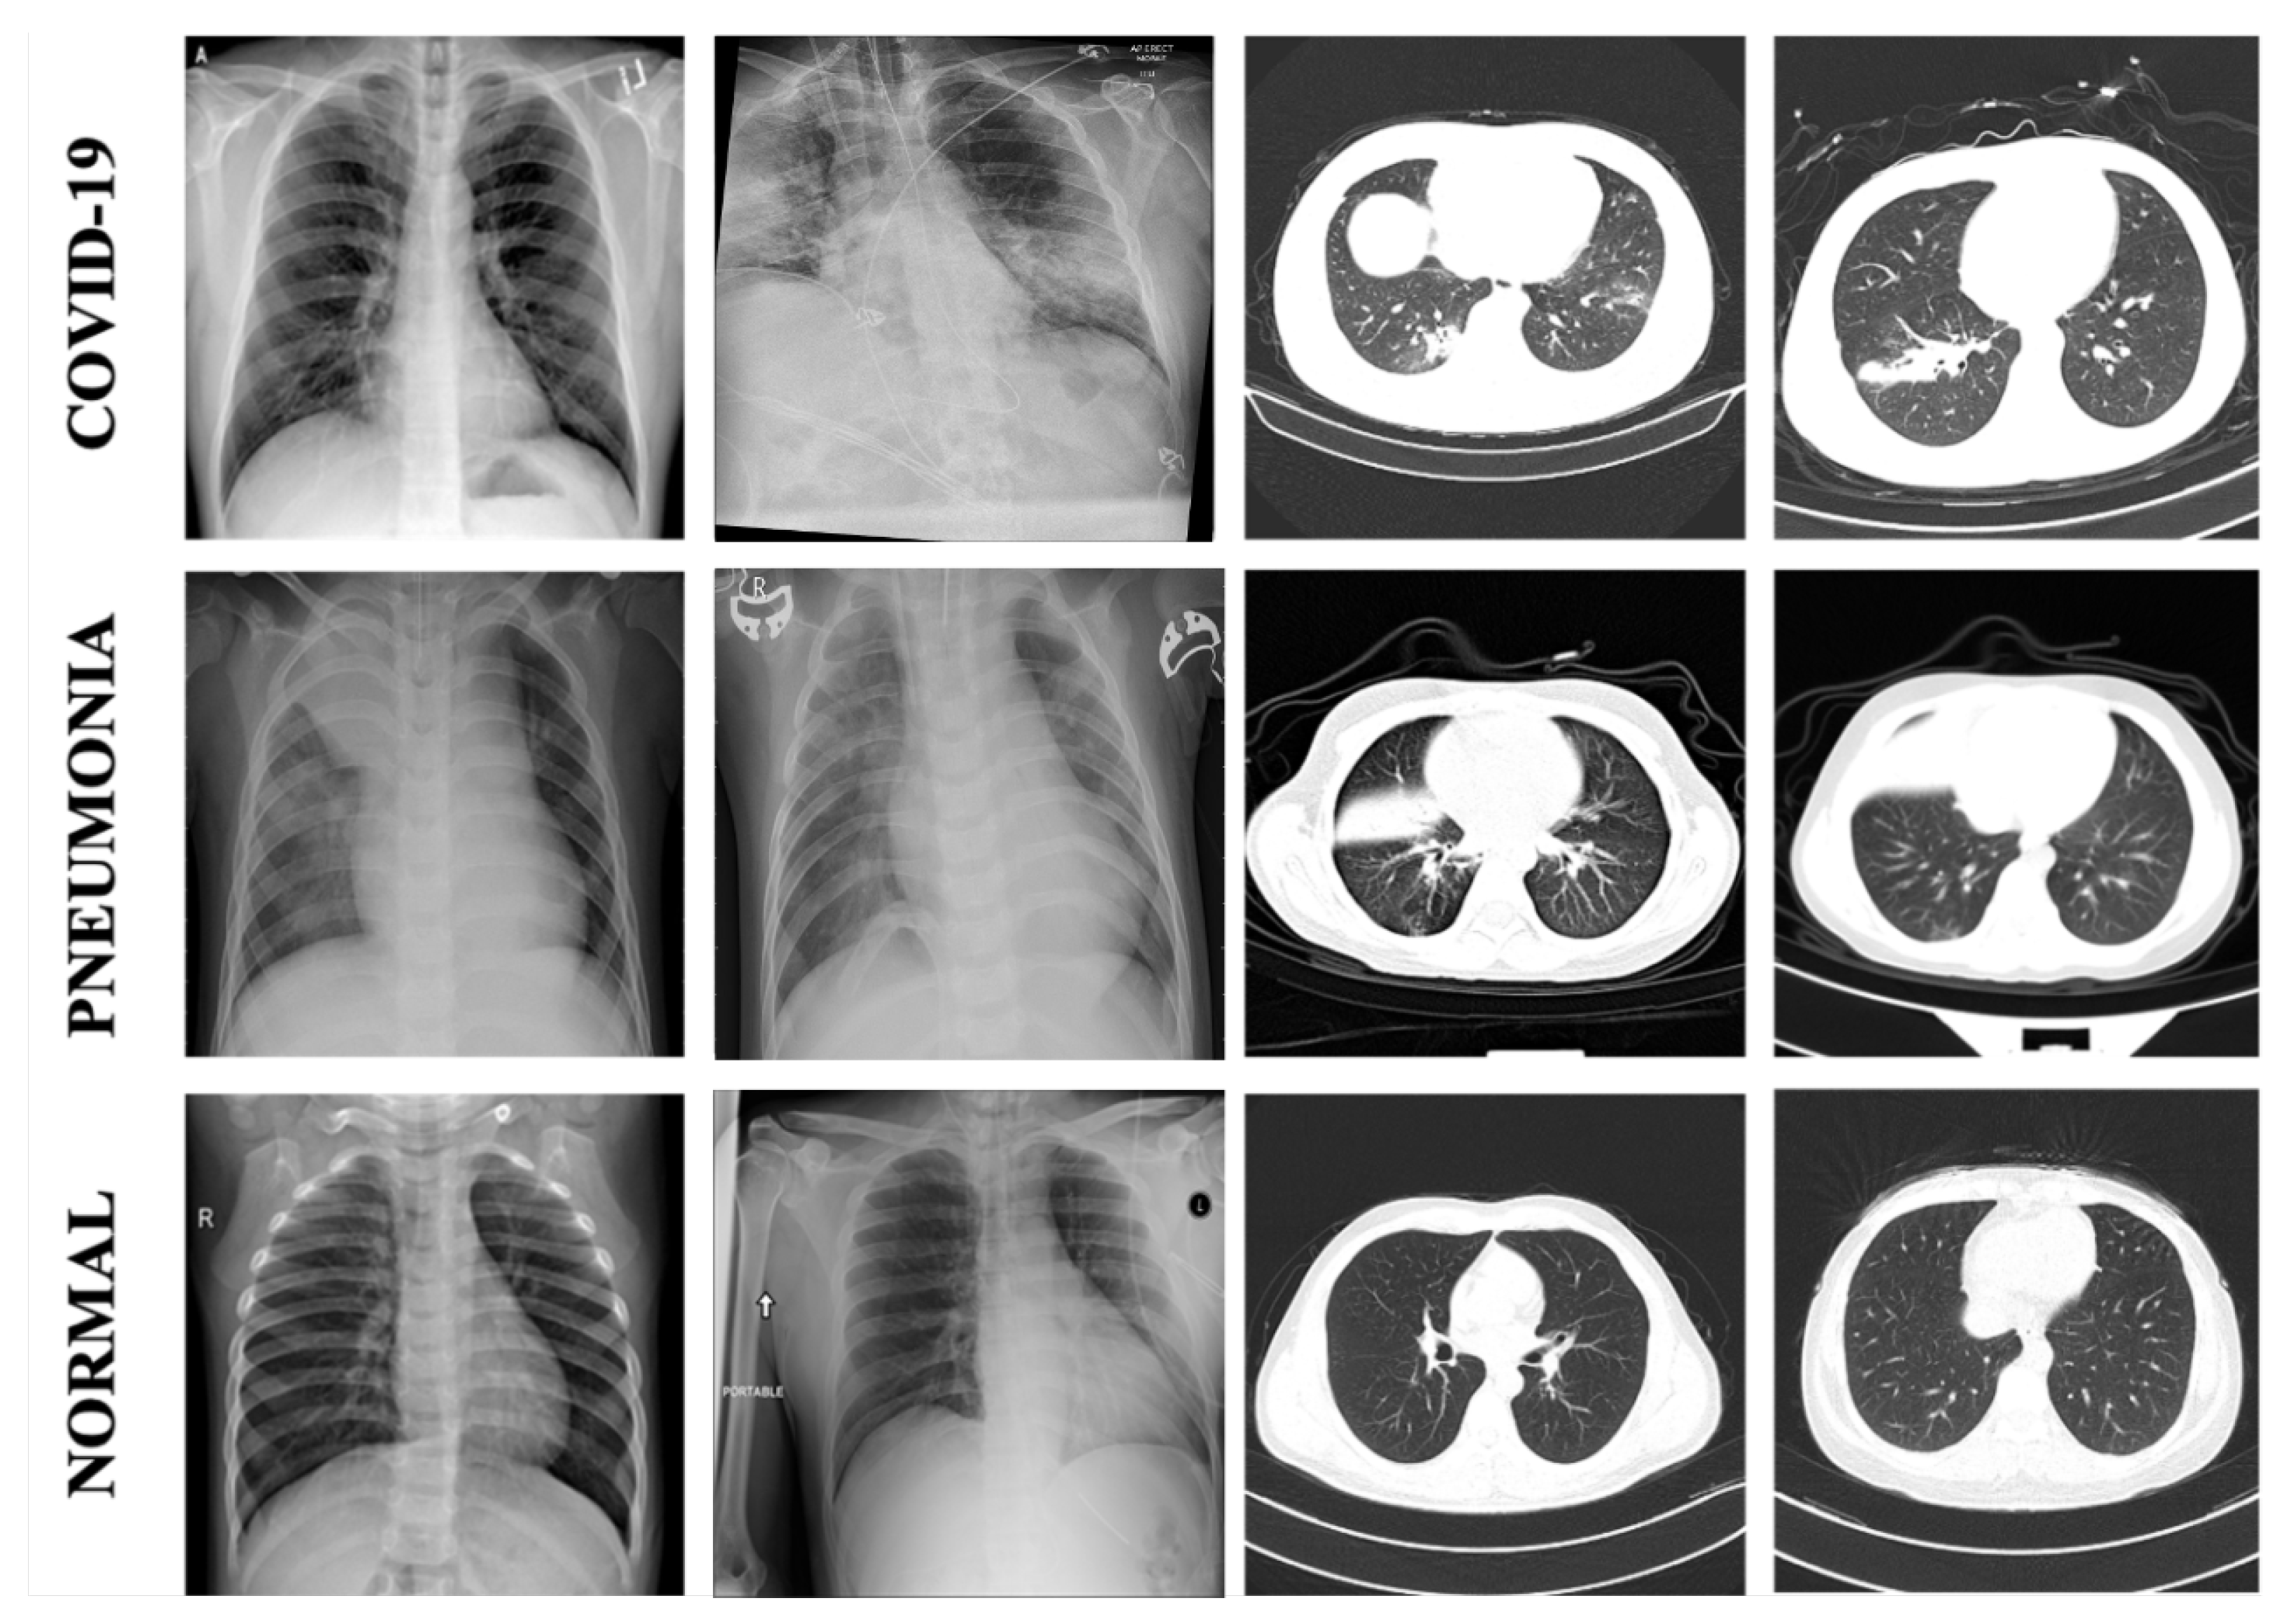

1. Introduction

2. Materials and Methods

2.1. Data Sets